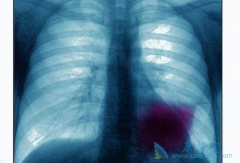

近年来,肺癌不再是老年人的专利,越来越多的年轻人也加入了肺癌的行列,甚至是不吸烟的年轻人。因早期肺癌大都无明显症状,有些患者甚至没有症状,导致很多人发现时已是中晚期。那么,肺癌晚期有多可怕?肺癌晚期临终前症状往往比较明显,常见的临终前症 ...